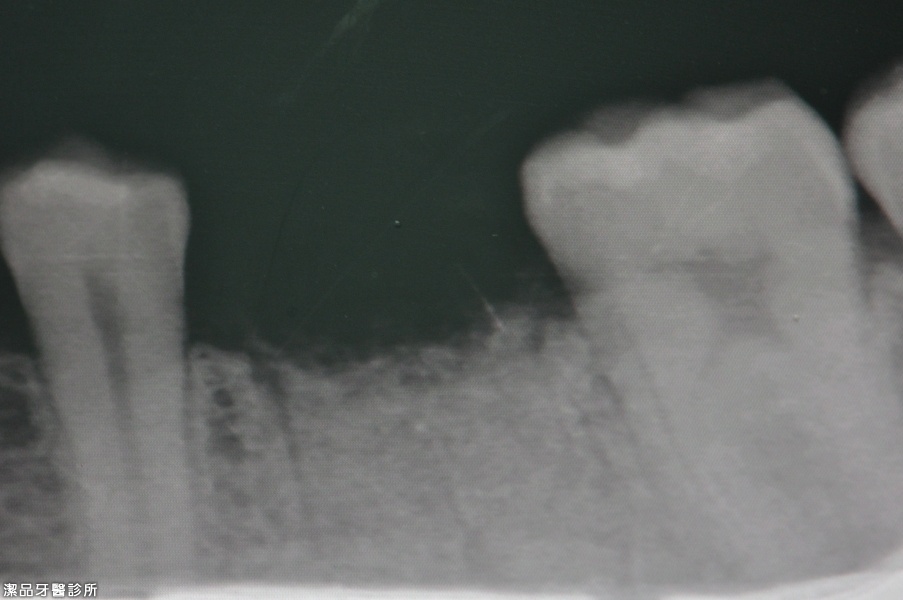

左下第一大臼齒根尖嚴重發炎

牙根嚴重發炎